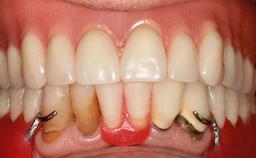

An 83-year-old man presented together with his caregiver at the dental department of the Medical University of Innsbruck, Austria with complaints of swelling in the right maxillary canine area and loss of retention of his 5-years-old mandibular denture. The patient had a significant medical history (20 years) of bipolar affective disorder with moderate depression (F 31.3) and dementia in Alzheimer’s disease (F 00.2). The patient had been in ambulant psychiatric therapy for his depressive illness for the past 20 years. He lived alone and had no children; his sister assisted with daily living. She reported that the patient exhibited compulsive hoarding behavior. In the previous two months, she had noted increasing disorientation and vertigo in the patient. She therefore accompanied him for a medical consultation at the Department of Psychiatry and Psychotherapy of the Medical University of Innsbruck. He was released home after a 6-week inpatient stay.

Prosthesis Type RDP

Defining Characteristics Fully edentulous lower jaw to be rehabilitated with an implant-borne removable overdenture

Interim Prosthesis during Healing Removable Removable